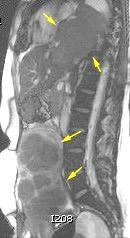

“Seudoquiste pancreático”

Seudoquiste pancreático

3 rasgos:

1. Conexión entre mediastino y lesión pancreática.

2. Derrame pleural

Matsusue E et al.Three cases of mediastinal pancreatic pseudocysts. Acta Radiol Open. 2016 .

3. Hallazgos de pancreatitis. Panda A et al. “Straddling Across Boundaries”. Thoracoabdominal Lesions: Spectrum and Pattern Approach.Curr Probl Diagn Radiol, 2015